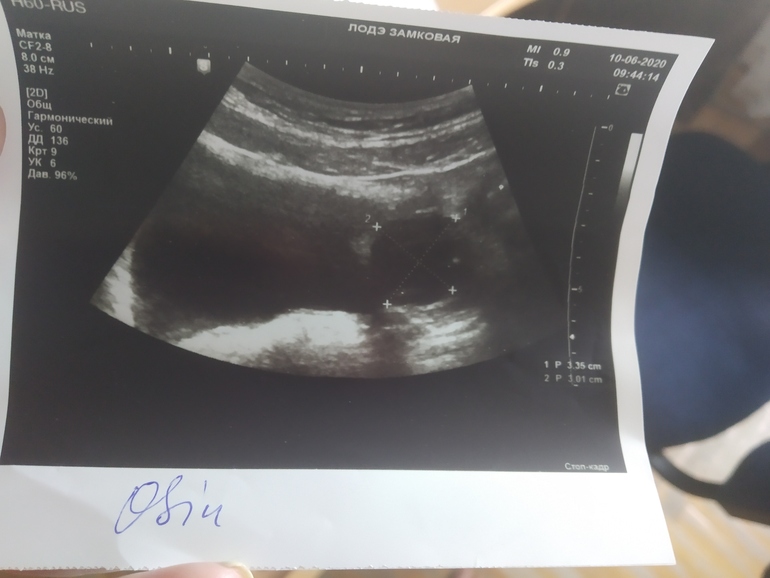

Фолликулярная киста или киста ЖТ

В снимках не разбираюсь, но вам даже врач не сказала какая у вас киста, или или..Фолликулярная это не лопнул доминантный фолликул, и надежды нет, так как нет О, киста ЖТ это О была и Надежда есть 🤔